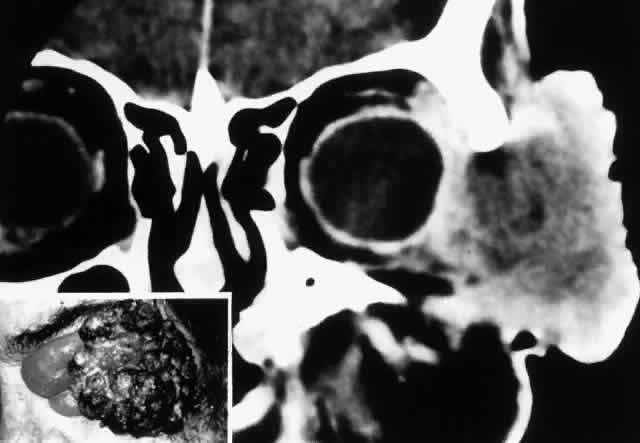

The clinical signs of squamous cell carcinoma (mean, 1 year) develop faster than the signs of basal cell carcinoma, consisting of focal hyperkeratotic lesions that slowly extend and ulcerate. They are more common at the lid margin and in the lower lid versus the upper lid, by a ratio of 1.4:1.56 Rarely, papillary forms may be seen. Orbital extension of squamous cell carcinoma is usually preceded by a history of chronic and repeated recurrence of lesions following treatment or long-term neglect by the patient (Fig. 7). Once the orbit is invaded, the tumor tends to spread along fascia and fatty planes relatively rapidly compared with basal cell carcinoma. Perineural invasion may occur and is associated with pain or ophthalmoplegia (Fig. 8).57–60 Also in contrast to basal cell carcinoma, squamous cell carcinoma is capable of metastasis, usually to the regional preauricular or submandibular lymph nodes. The incidence of regional spread varies from 1% to 21%, but is generally closer to the lower figure. In a review of large series documented in the literature, the overall mortality rate was found to be approximately 15%.56 Management of squamous cell carcinoma of the lid is usually surgical, with care being taken to obtain adequate controlled margins with the use of frozen sections or Mohs' technique. Fitzpatrick and associates61 reported a control rate of 93% with radiotherapy; however, squamous cell carcinoma is thought to be less sensitive to radiotherapy than basal cell carcinoma, so higher doses are usually recommended. For deep orbital invasion, radical therapy is indicated; this may constitute either exenteration or radical radiotherapy, according to the circumstances outlined in the discussion on basal cell carcinoma.

Fig. 7. A 61-year-old chronic alcoholic man presented with a fungating, putrefying, left temporal mass(inset) that extended into the adjacent orbit and flattened the globe, as shown on coronal CT scan. It proved to be a squamous cell carcinoma of the skin associated with cervical and mediastinal adenopathy. He underwent radical local radiotherapy, which led to regression of the local lesion. (Rootman J, Ragaz J, Cline R, Lapointe JS: Metastatic and secondary tumors of the orbit. In Rootman JR (ed): Diseases of the Orbit: A Multidisciplinary Approach, pp 405–427. Philadelphia, JB Lippincott, 1988.)

Fig. 8. A 73-year-old man treated 3 years previously with excision of a squamous cell carcinoma in the left supraorbital region had recurrence of tumor, which was again excised. He developed progressive pain and tingling in the forehead, vertical diplopia, and finally general malaise lasting 18 months, ultimately requiring hospitalization. He was treated with corticosteroids for presumed Tolosa-Hunt syndrome, showed minimal improvement, and was discharged. Over a 2-month period, he developed decreased vision, ptosis, and bulging of the eye. On presentation he had vision of 20/80 with a relative afferent pupillary defect. There was hypesthesia in the distribution of cranial nerve V1 and hyperesthesia in V2. He had a palpable fixed cord in the forehead in the distribution of the supraorbital nerve, complete ptosis, ophthalmoplegia, and 7 mm of proptosis (A). CT scan showed local infiltration along the supraorbital nerve (B, arrow), with extension of a soft tissue mass along the orbital roof to the orbital apex (C), through a widened superior orbital fissure, and into the cavernous sinus (D). An orbital biopsy revealed cords of squamous cells (E) (H & E, × 80) and evidence of infiltration inside a small branch nerve sheath (F) (H & E, × 80). A single fraction of 10 Gy was given as palliative treatment for pain control.